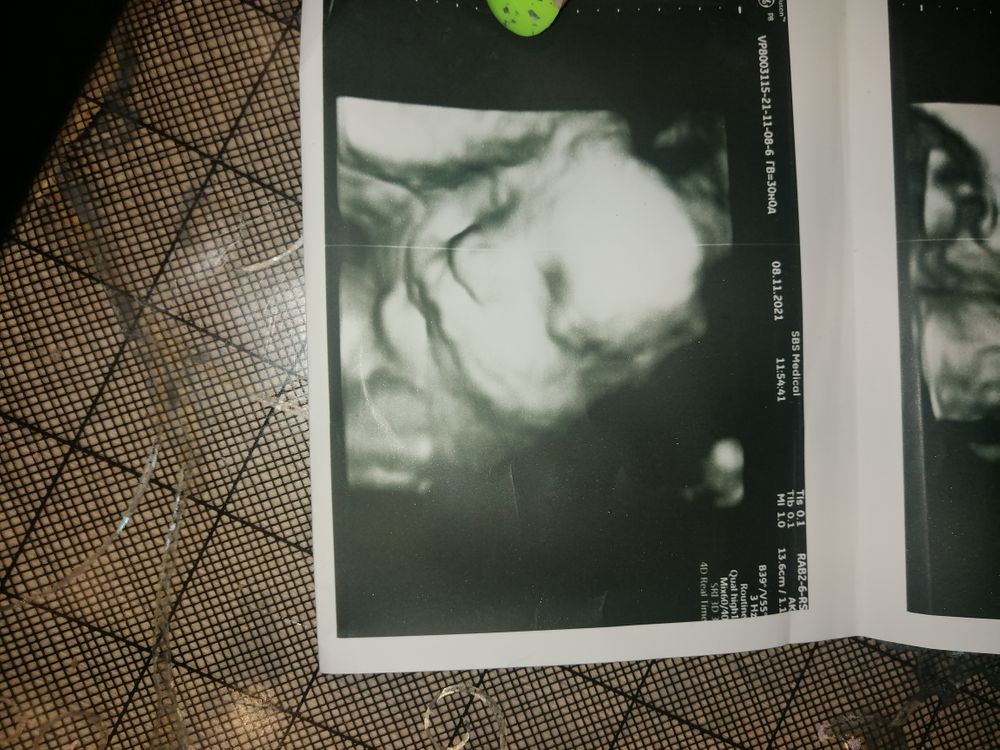

Я делала в 25 ,но и то получилось кое как так как она лицом к спине лежала и руками закрывалась ) Узистка приказывала на аппарате своём 3д на сроке 31-32 и хорошо видно было четко прям ,но это наверное ещё от положения зависит ) Изображение Изображение